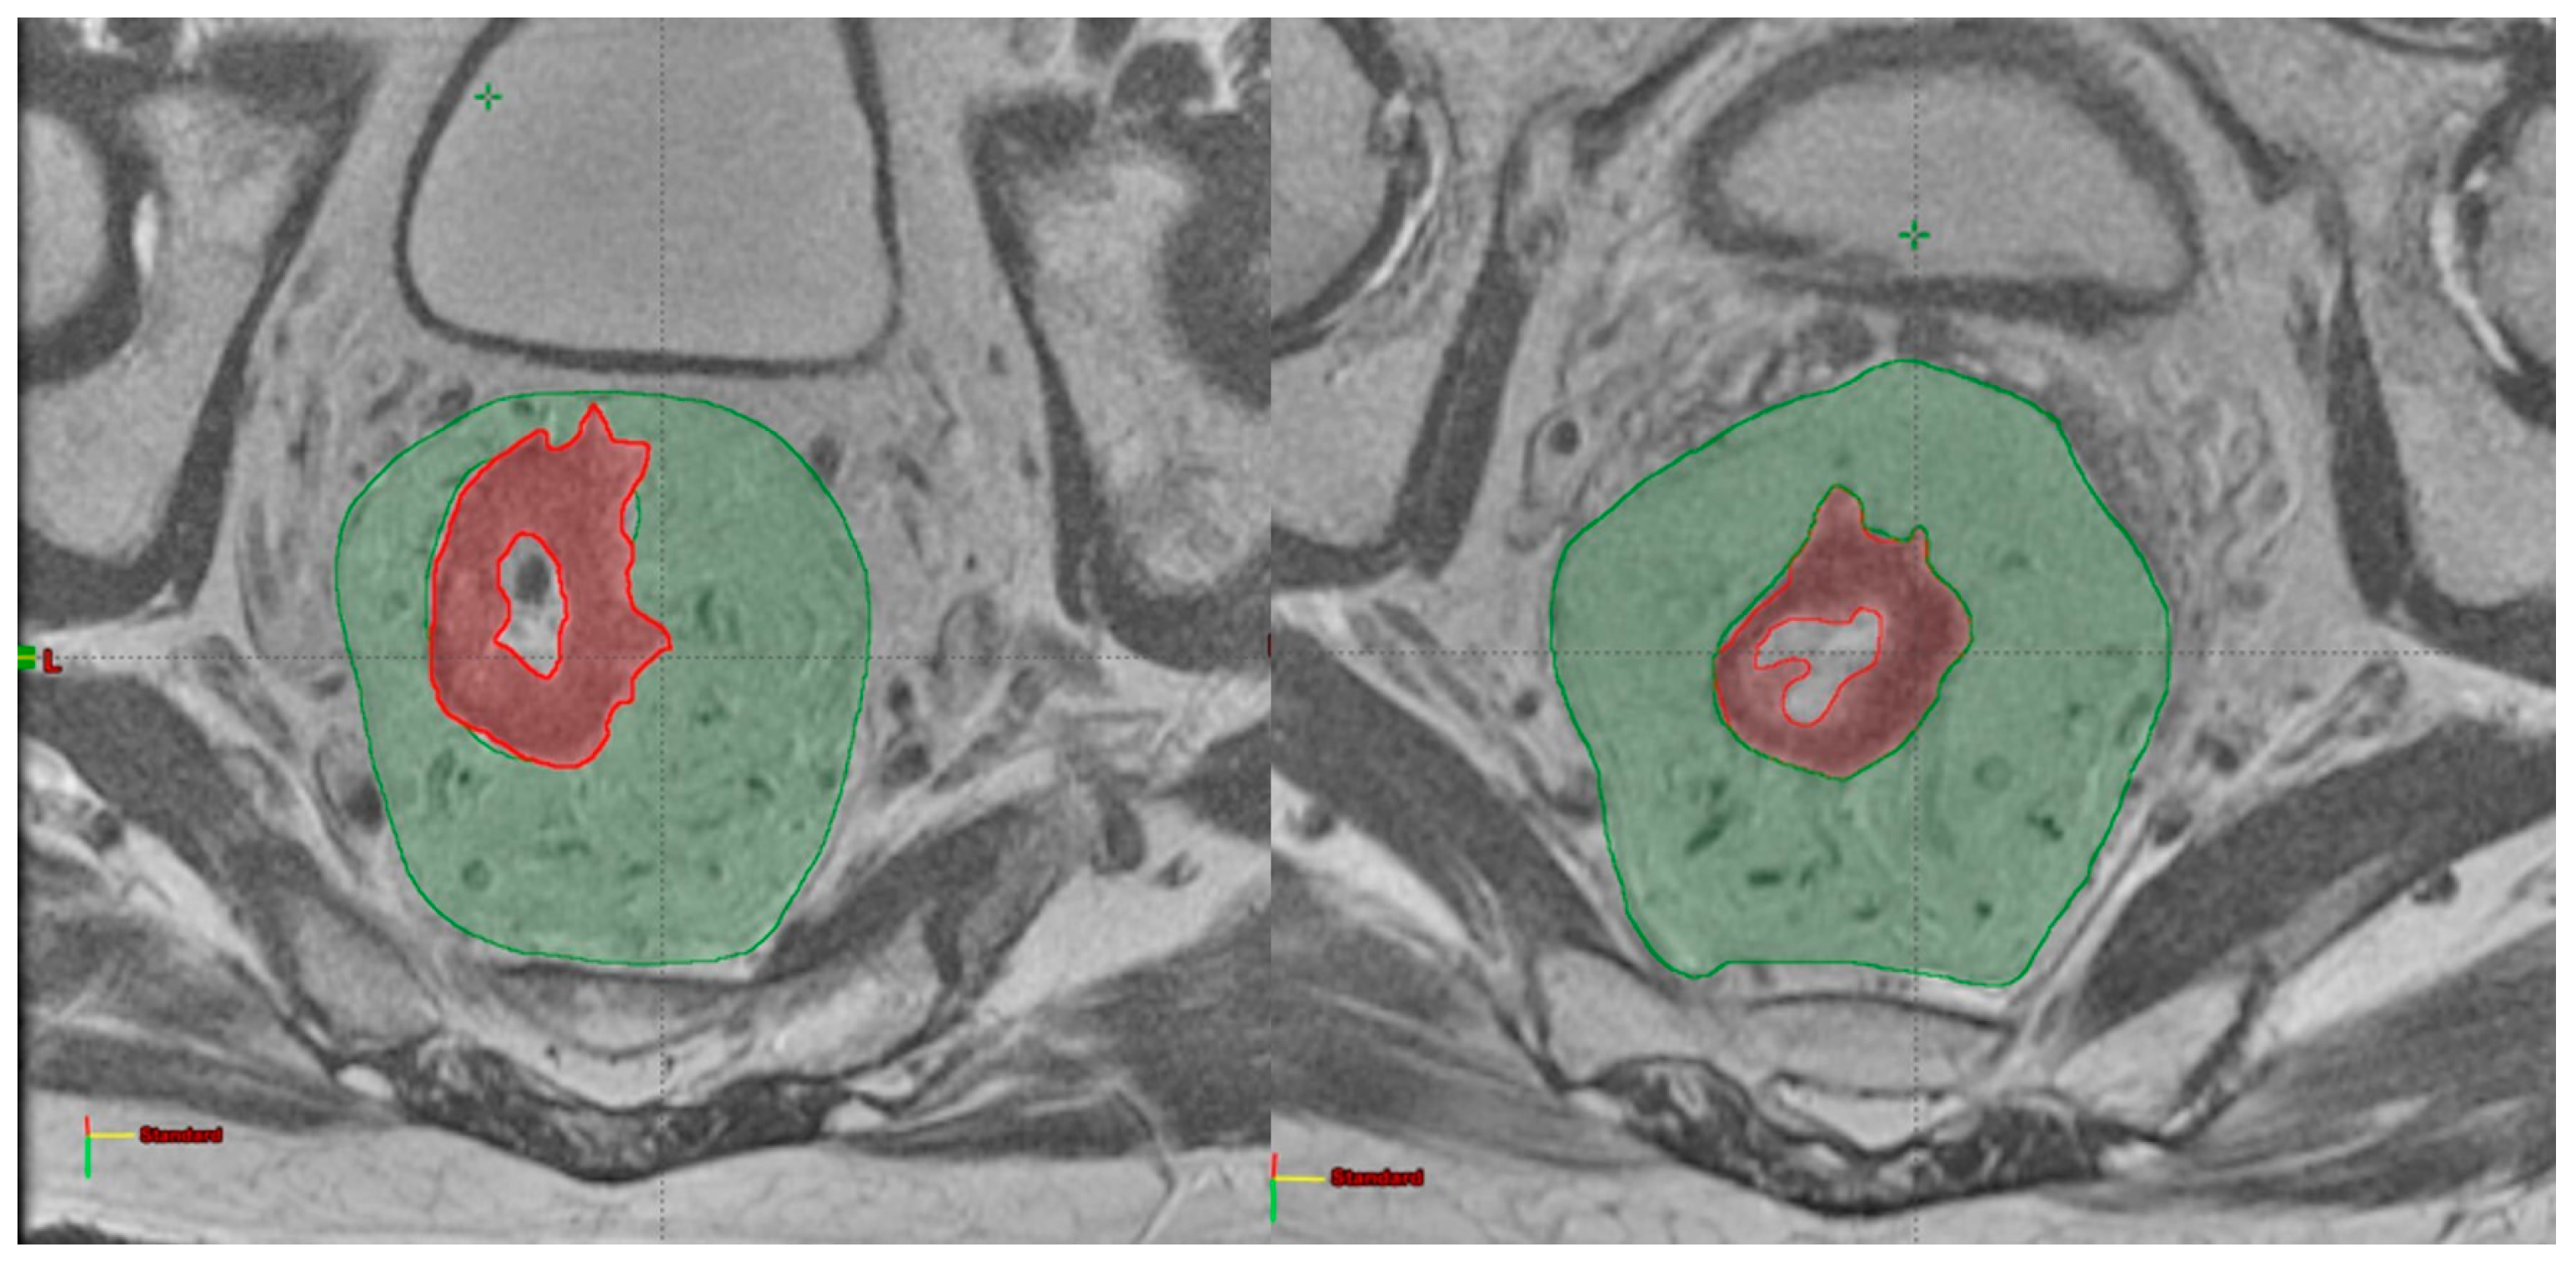

2.2. Image Analysis